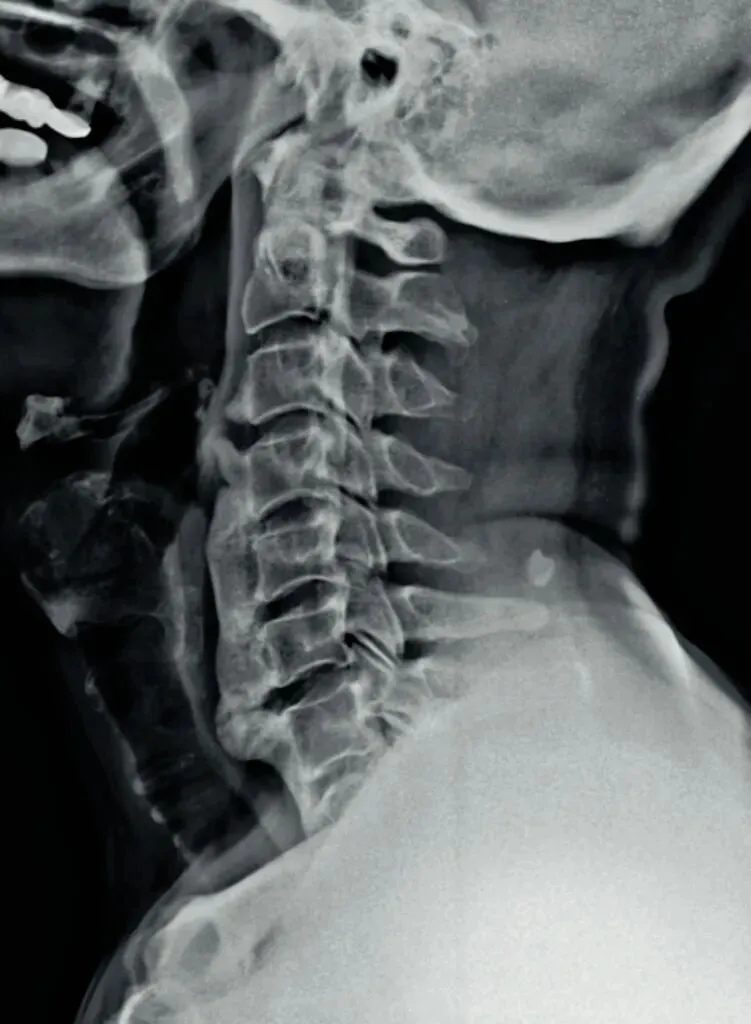

一骨是是我们主要在颈椎侧位X线片中观察椎体的形态与结构,查看椎体是否规则,

椎体边缘有无变尖或呈唇样改变的骨质增生。

椎体骨质有无破坏,密度是否正常,如肿瘤或者感染。

椎体的高度是否均匀,有无压缩变形。椎体高度减小可能提示骨质疏松、压缩性骨折

或椎体的发育异常等。